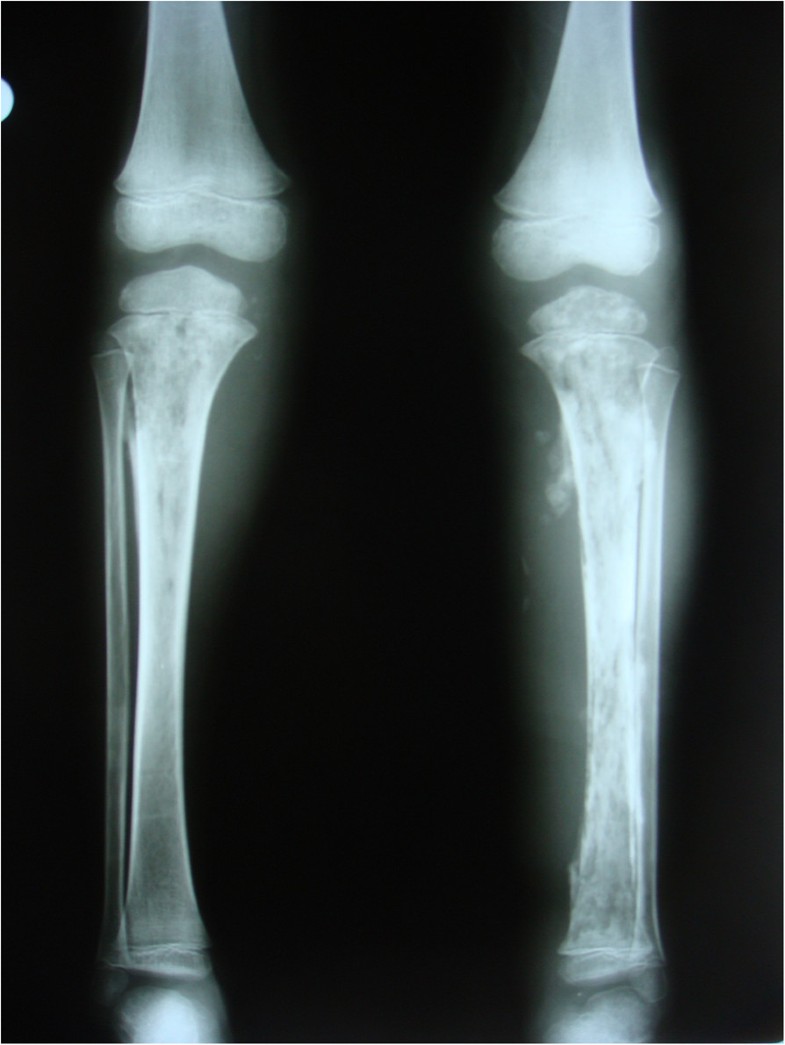

From jmedicalcasereports.biomedcentral.com

Bilateral acute tibial osteomyelitis in a patient without an underlying Osteomyelitis Case From a case of acute osteomyelitis in a tarsal bone under an infected ulcer in a diabetic patient, we can observe distinct. When osteomyelitis is diagnosed, it is classified as acute if the duration of the illness has been less than 2 weeks, subacute for a duration of 2 weeks to 3 months, and chronic for a longer. It may. Osteomyelitis Case.